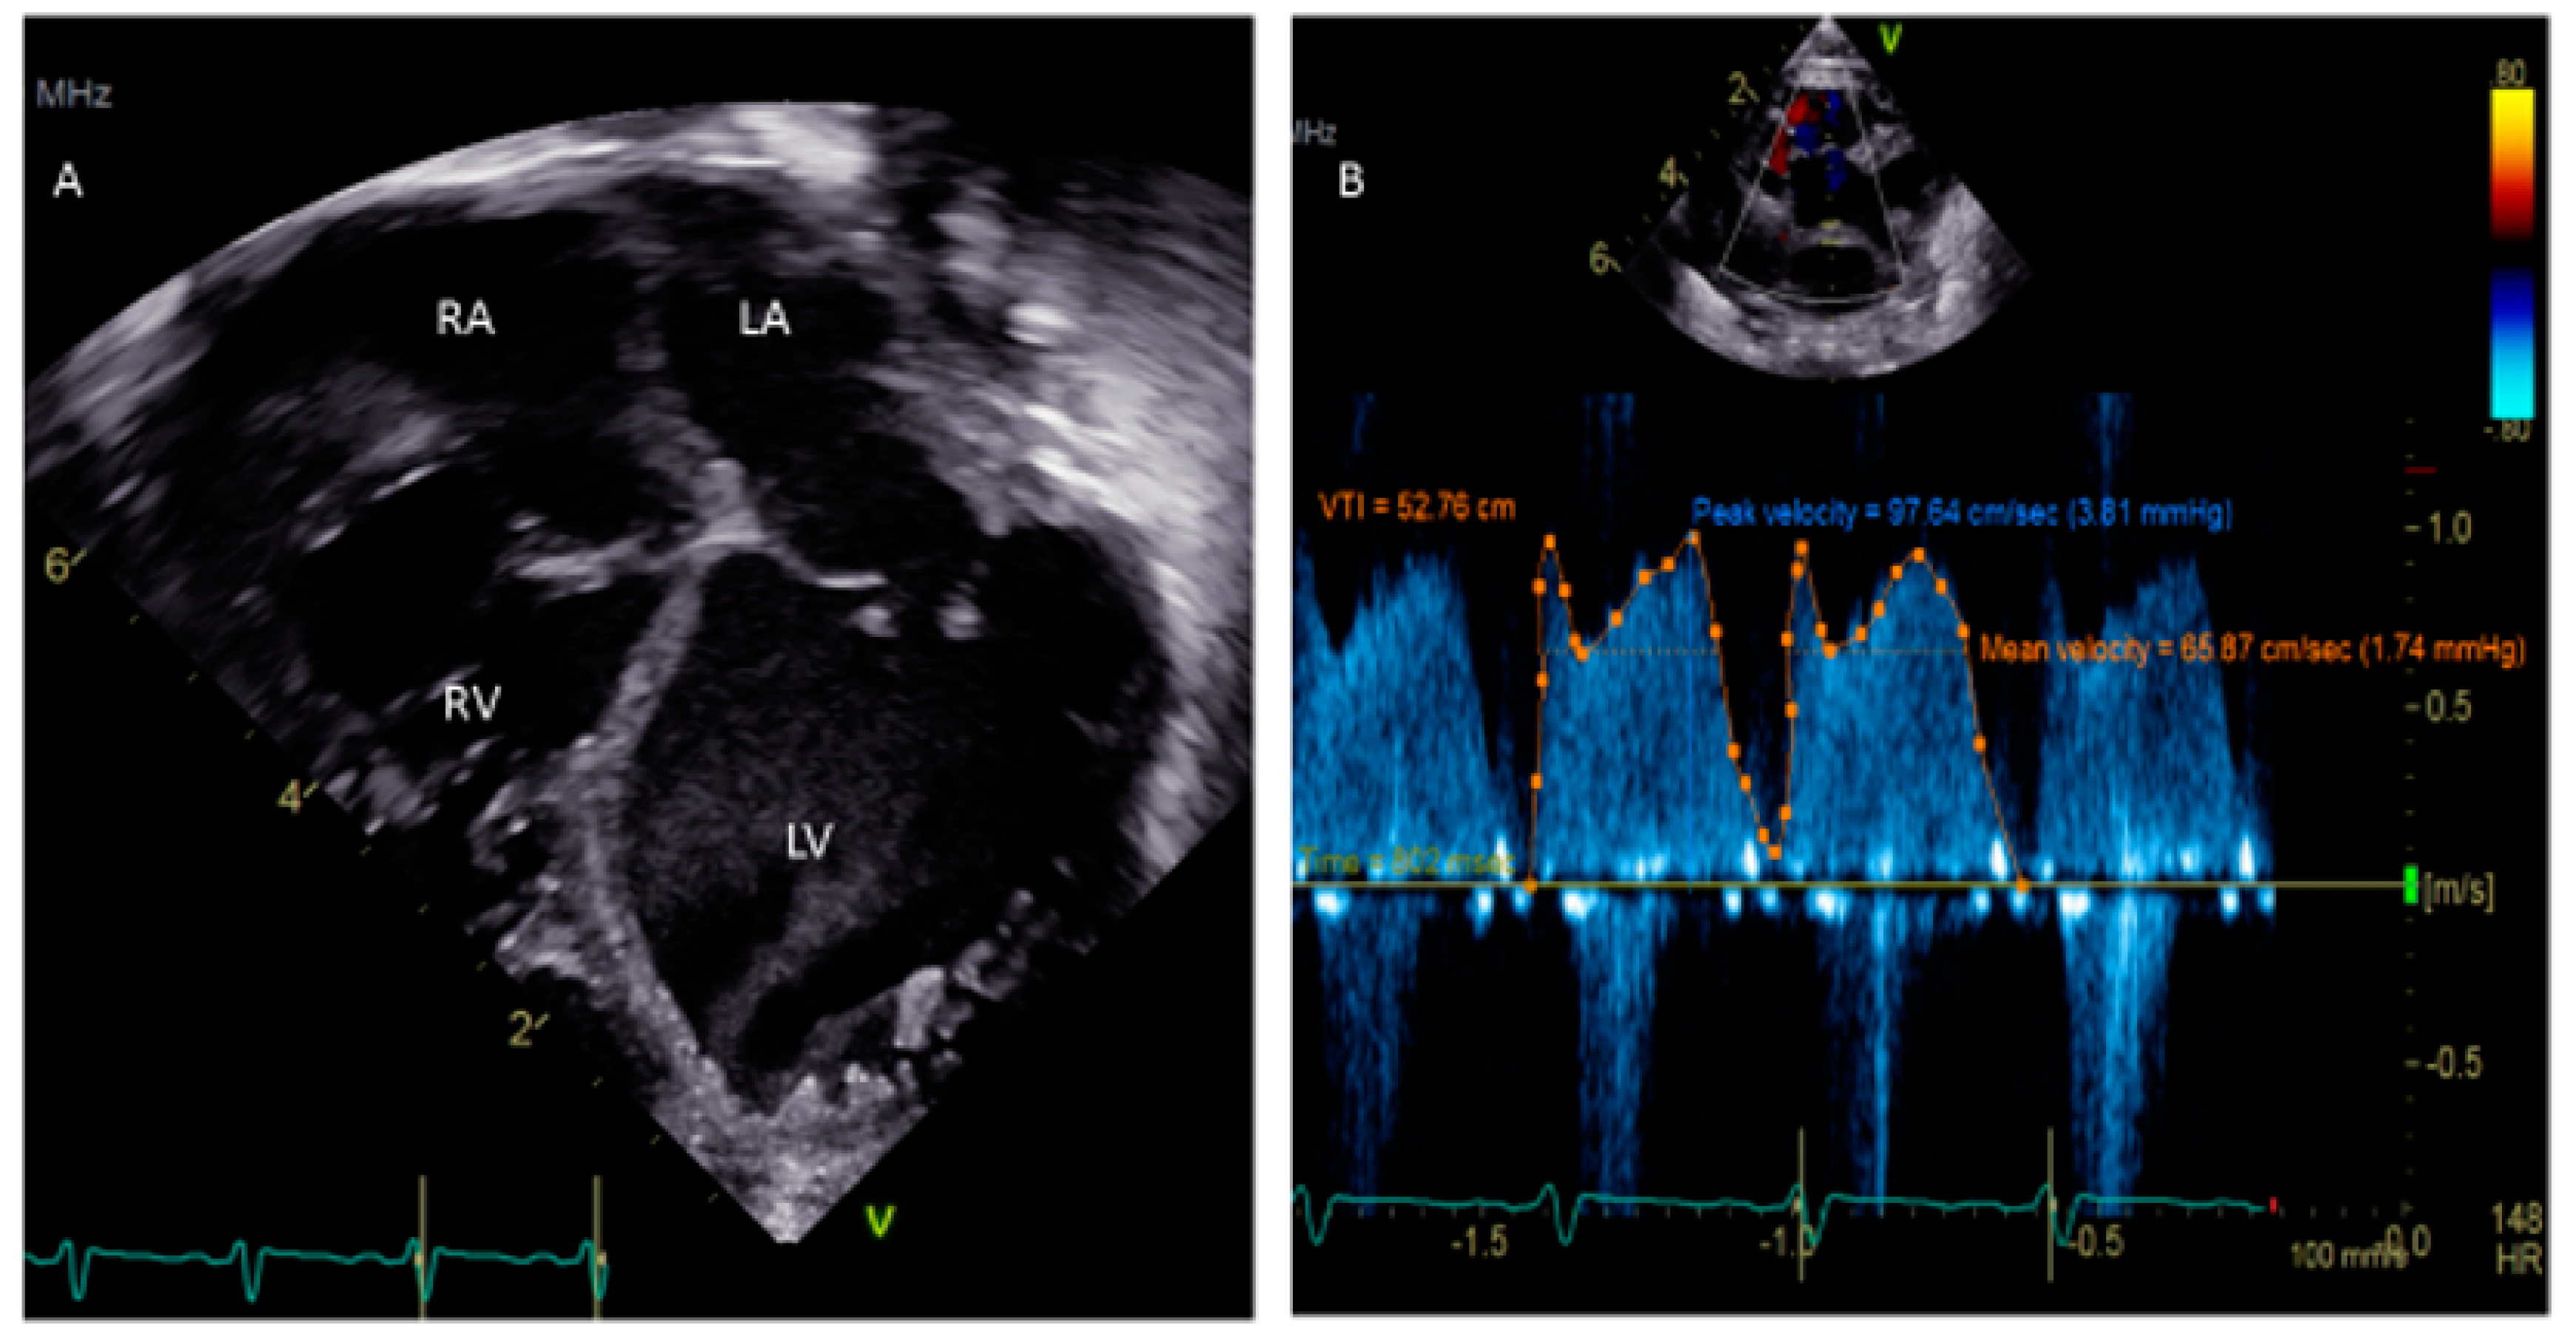

- Silvestry, F.E. Guidelines for the echocardiographic assessment of atrial septal defect and patent foramen ovale from the American Society of Echocardiography for cardiac angiography and interventions. J. Am. Soc. Echocardiogr. 2015, 28, 910–985. [Google Scholar] [CrossRef]

- Rana, B.S.; Shapiro, L.M.; McCarthy, K.P.; Ho, S.Y. Three-dimensional imaging of the atrial septum and patent foramen ovale anatomy: Defining the morphological phenotypes of patent foramen ovale. Eur. J. Echocardiogr. 2010, 11, 119–125. [Google Scholar] [CrossRef]

- Giannopoulos, A.; Gavras, C.; Sarioglu, S.; Agathagelou, F.; Kassapogelou, I.; Athanassiadou, F. Atrial septal aneurysms in childhood: Prevalence, classification, and current abnormalities. Cardiol. Young 2014, 24, 453–458. [Google Scholar] [CrossRef]